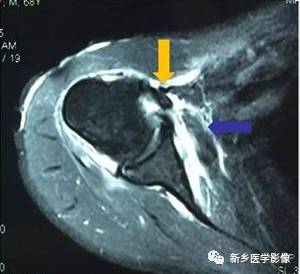

病例九:

红色箭头:冈上肌腱损伤

黄色箭头:二头肌腱长头腱脱位

蓝色箭头:肩胛下肌腱损伤